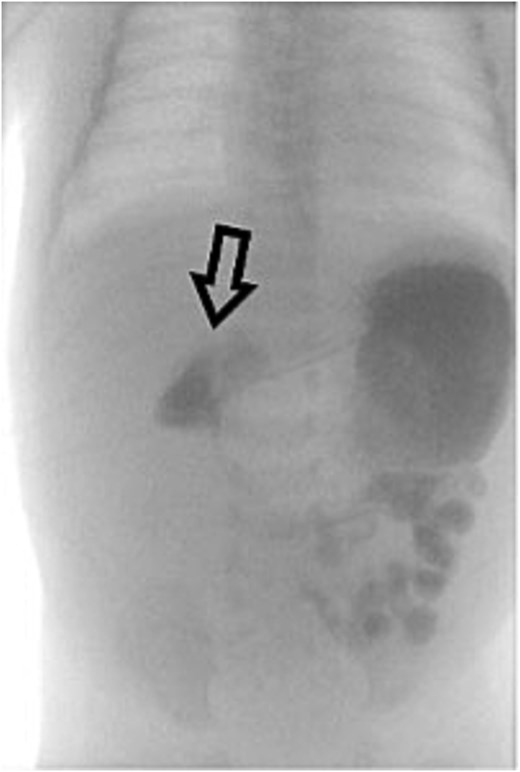

On Day 3 of life, she developed multiple episodes of bilious emesis and passed meconium-stained stools. An abdominal radiograph revealed gas-filled, non-distended bowel loops on the right and absence of small bowel gas on the left (Fig. 1), raising suspicion for malrotation. An upper GI (UGI) series confirmed abnormal duodenal positioning and obstruction, suggestive of malrotation with volvulus (Fig. 2). Emergent Ladd’s procedure was performed, revealing midgut volvulus with cloudy peritoneal fluid but viable bowel.

Initial UGI series demonstrates abnormally dilated descending duodenum with no contrast crossing the midline. Findings are consistent with obstruction.